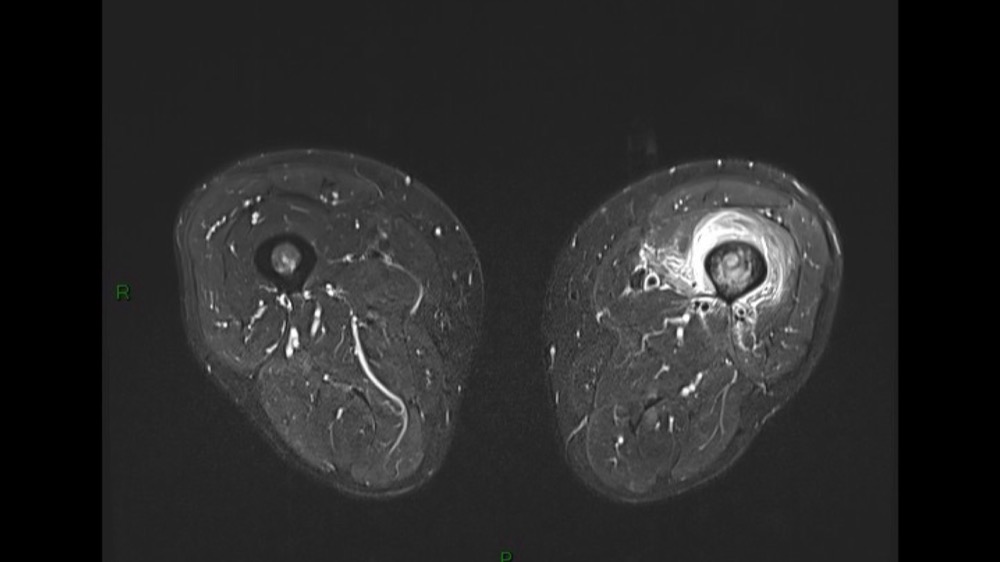

Lombo-cruralgie subaiguë trompeuse

Pascalie Jallerat 22/06/2020